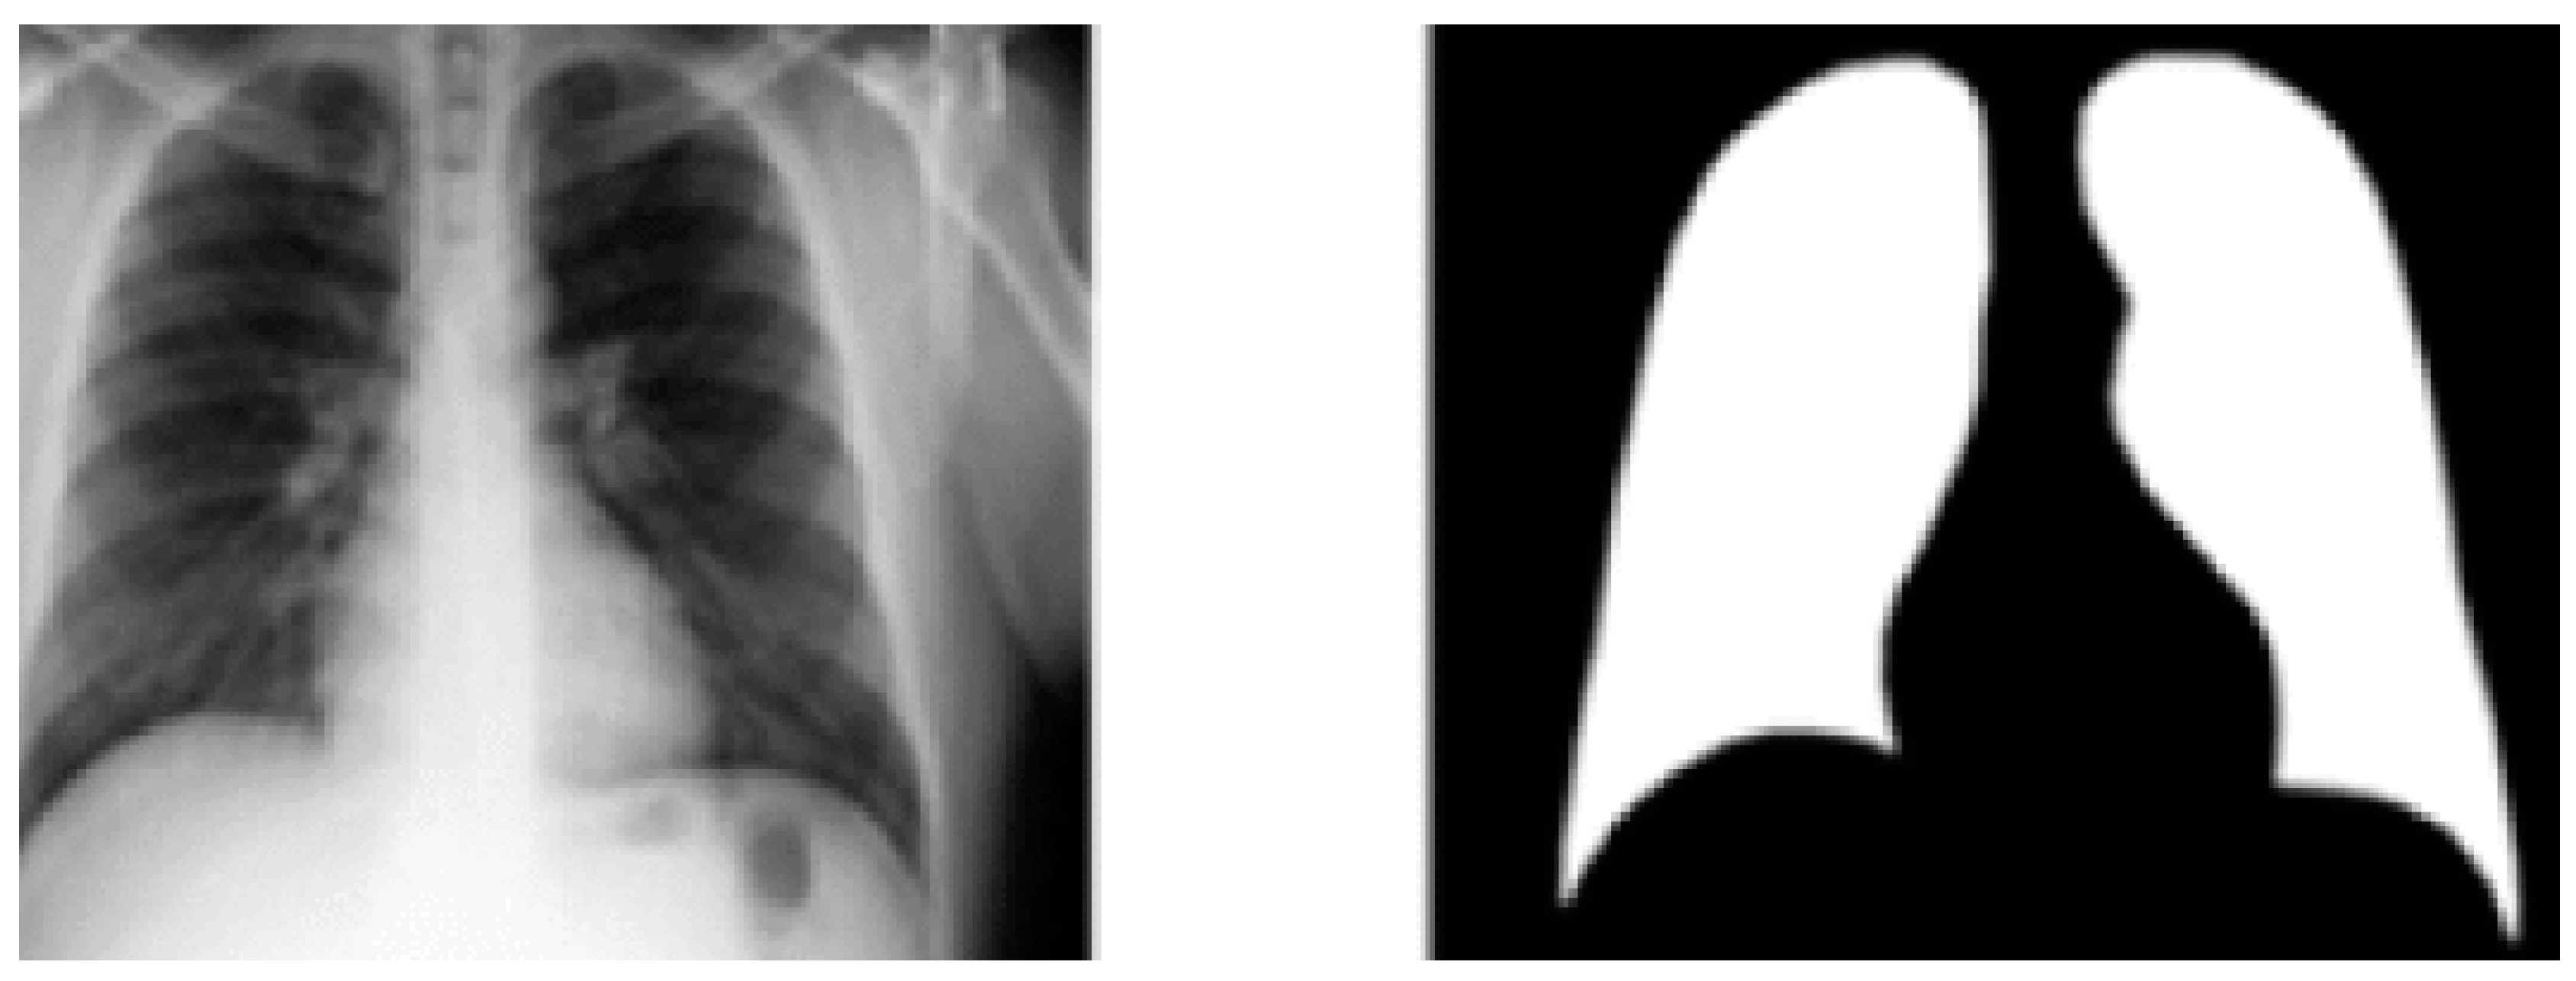

In this research, the Kaggle X-ray dataset and pulmonary mask database [29] are utilized for training the pulmonary segmentation method. Eight hundred X-rays and their analogous ground truth pulmonary masks are presented. All masks were annotated by expert radiologists and labelled by medical experts; X-ray instances and their analogous masks are depicted in Figure 2. The database includes 460 healthy X-ray images and 340 diseased pulmonary X-ray images. Consequently, BoxENet model are trained with both X-ray images.

Figure 2. X-ray instance and their analogous mask from the Kaggle database.